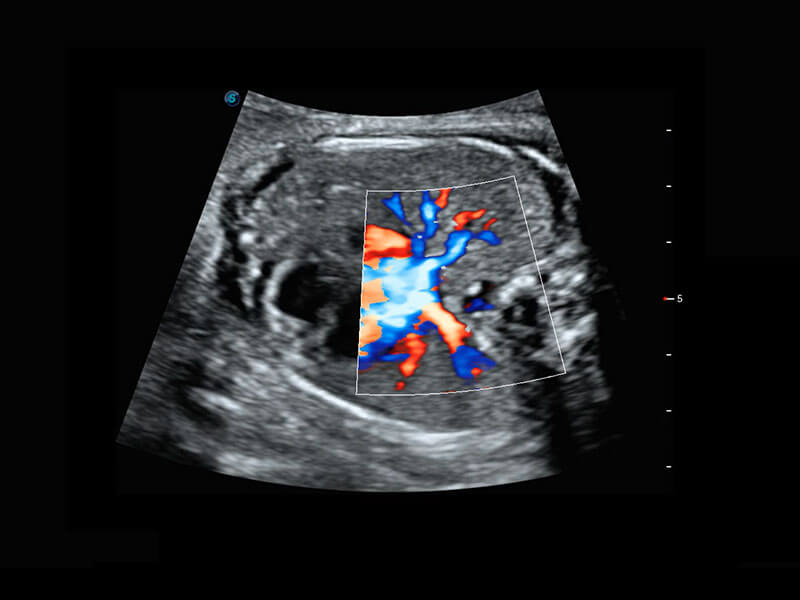

胎心筛查

P60搭载一系列胎儿心脏成像技术,实现更精细的胎儿心脏评估。

• 四腔切面

• 四腔心血流

• 右室双出口

• 胎心容积成像